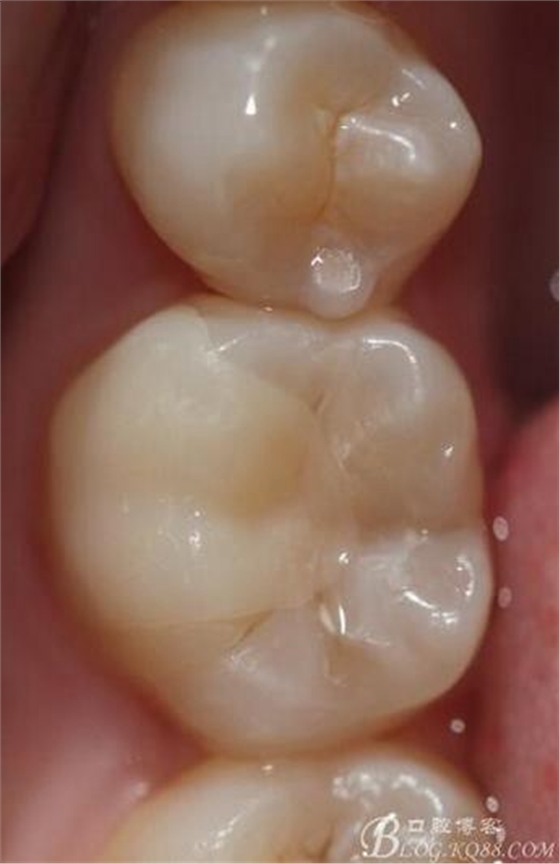

粘接 去除多余的粘結(jié)劑 進行光照 調(diào)HE 一周后進行拋光

粘接后X線片

復(fù)診拋光 很容易看到邊緣線,原因是主要有兩個:一-瓷塊選擇不準(zhǔn)確,目前我們單位瓷塊顏色單一。二- 粘結(jié)劑,選擇和牙體顏色不一致的。我選擇的偏白,所以邊緣白線較明顯。

總結(jié):歷時2周時間結(jié)束,比較累。整體感覺沒有想象中那么好,總也做不出樹脂嵌體的那種渾然天成的感覺。